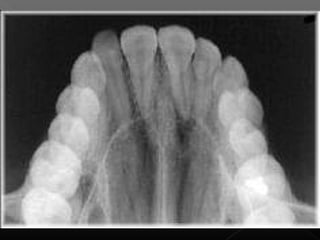

Este documento describe las radiografías oclusales y panorámicas, incluyendo sus usos y técnicas. Las radiografías oclusales se utilizan para examinar grandes áreas de los maxilares y se colocan entre las superficies oclusales cuando el paciente muerde suavemente. Las panorámicas permiten ver los maxilares y la mandíbula en una sola imagen. El documento también explica diferentes tipos de radiografías periapicales y sus ángulos de inclinación.